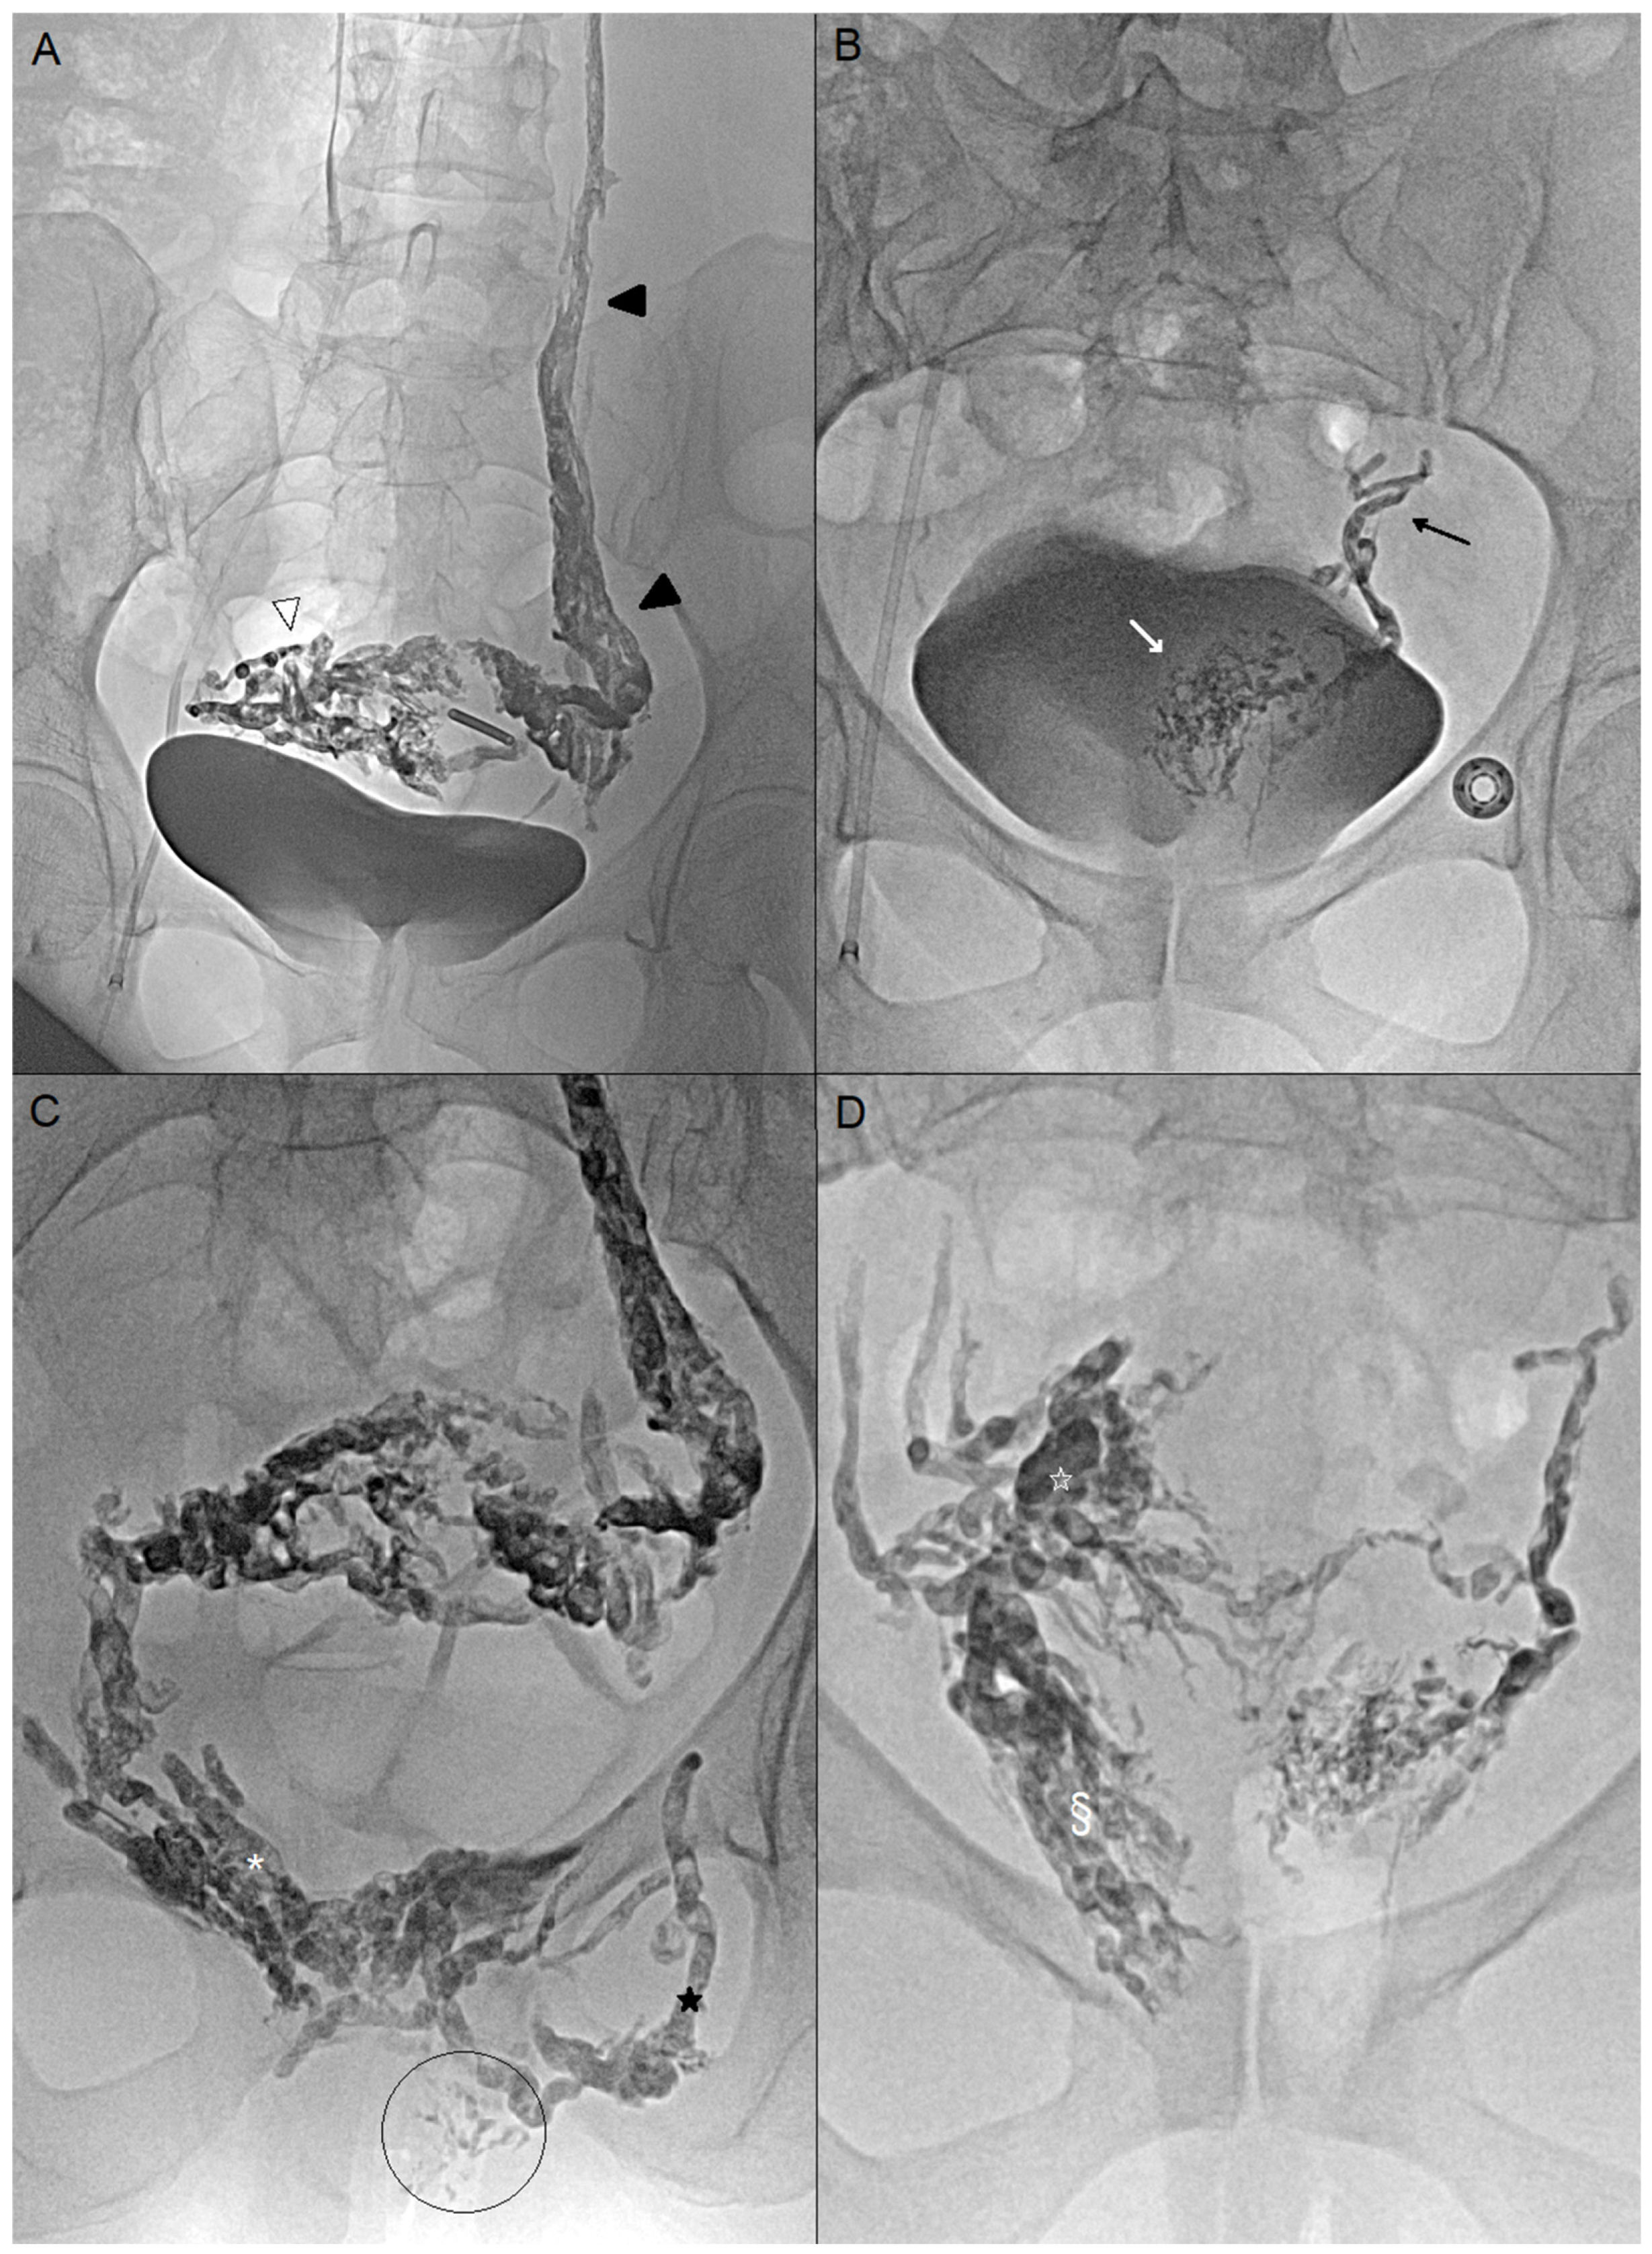

Figure 1. A 35-year-old woman (case n°6), G1P1, presenting with a 3-year history of chronic pelvic pain. Significant improvement in symptoms was achieved following endovascular embolization. However, dyspareunia (VAS 7/10) and postcoital pain (VAS 6/10) persist. (A) Oblique coronal MRI in the vaginal axis, LAVA FS sequence following gadolinium-based contrast injection (GE Systems, Signa Hero), demonstrating persistent right perivaginal varices (white arrow). The embolic agent (Onyx) is clearly visualized on this 3D gradient-echo sequence as a susceptibility artifact in the left perivaginal varices (white arrowhead). (B) Percutaneous puncture of right perivaginal varices (dark arrowhead) with a n18-gauge needle (dark arrow) under endovaginal guidance (*). Slow injection of iodinated contrast agent demonstrating opacification of the entire perivaginal and peri-uterine variceal network on the right side.